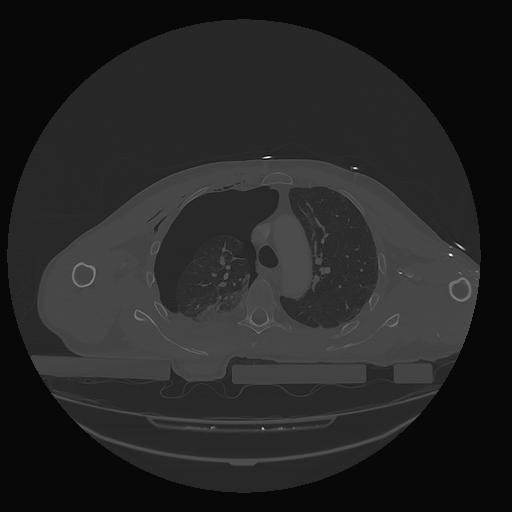

31 PULMON,CE,Vol,1.0,PULMON,,